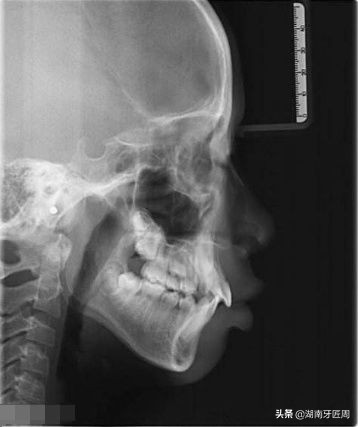

头颅侧位片

牙片主要有全景片(大片)和根尖片(小片)和头颅侧位片,必要时可做口腔科电子计算机X线体层摄影(CBCT)辅助检查。